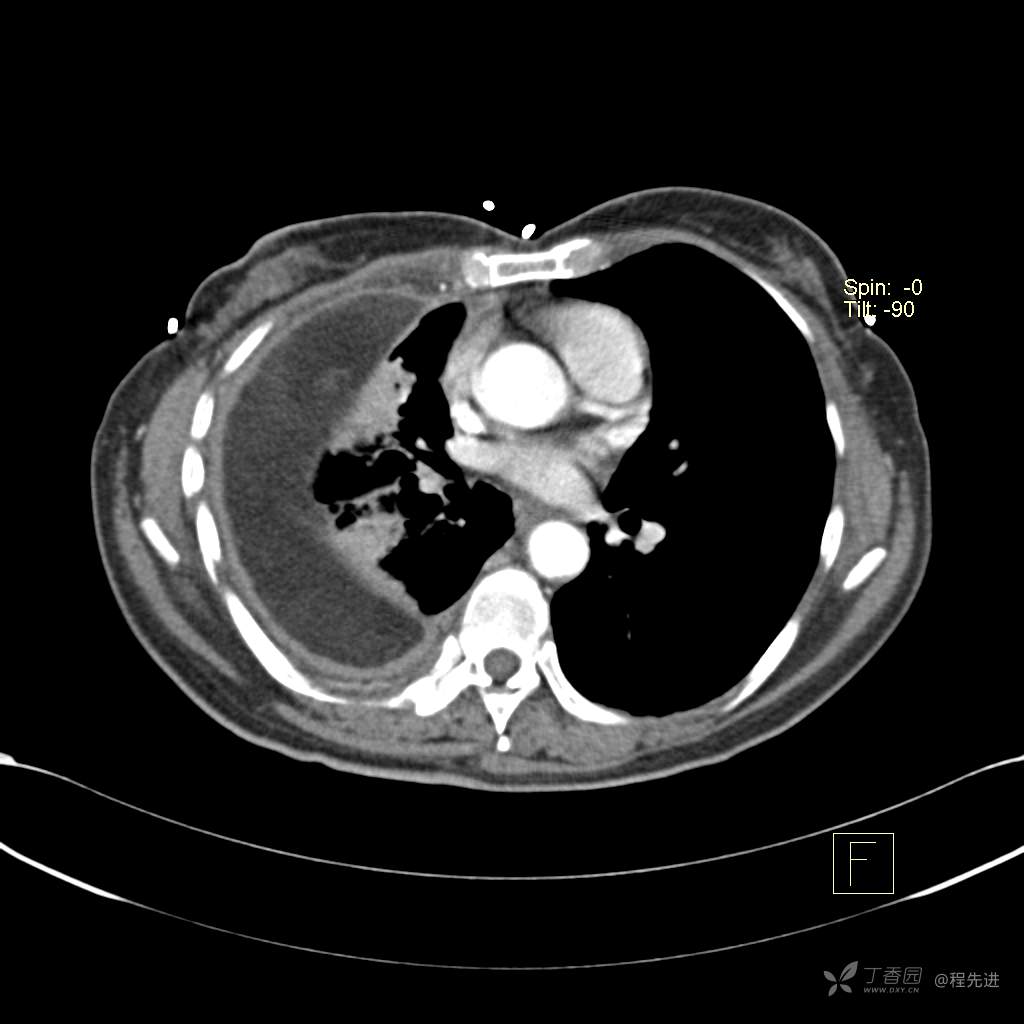

患者性别:女

患者年龄:51岁

简要病史:胸闷半年